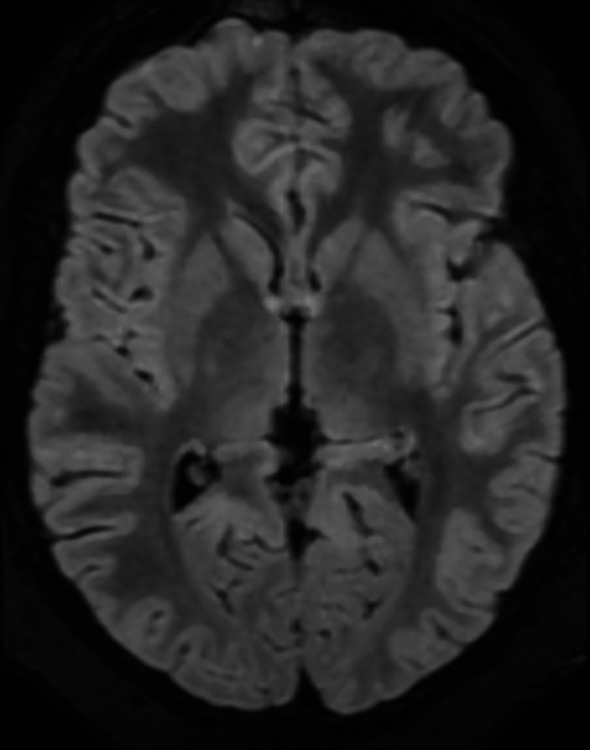

Wernicke-Korsakoff syndrome is a neurological disorder caused by thiamine (vitamin B1) deficiency. This encephalopathy is typically suspected in alcoholics adults, but it is important to remember that other less known and suspected causes can determine the development of the non-alcoholic Wernicke's encephalopathy. In non-alcoholic patients, the primary causes of Wernicke's encephalopathy include hyperemesis gravidarum, restrictive diets and malnutrition, cancer, post-operative complications following bariatric surgery. Few data are reported regarding non-alcoholic thiamine deficiency, especially within the paediatric population. We describe the case of an 11-year-old Caucasian male with obesity who experienced prolonged emesis after the beginning of a strictly hypocaloric dietary regimen. This resulted in biliary colic episodes and subsequent necessity for cholecystectomy. The day after surgery, the patient developed acute visual impairment, horizontal nystagmus and diplopia, which were attributed to thiamine deficiency. Wernicke's encephalopathy was suspected, so a blood sample was immediately collected to assay thiamine levels and empiric thiamine supplementation was started. Already from the day after the beginning of the treatment, the patient showed a significant improvement in his clinical conditions. This case study delineates clinical presentation, diagnosis, and treatment of our patient and provides information regarding the red-flag risk factors of non-alcoholic Wernicke's encephalopathy in children. The aim is to increase the likelihood of suspecting the diagnosis and to promptly start the therapy, which is both simple and lifesaving.